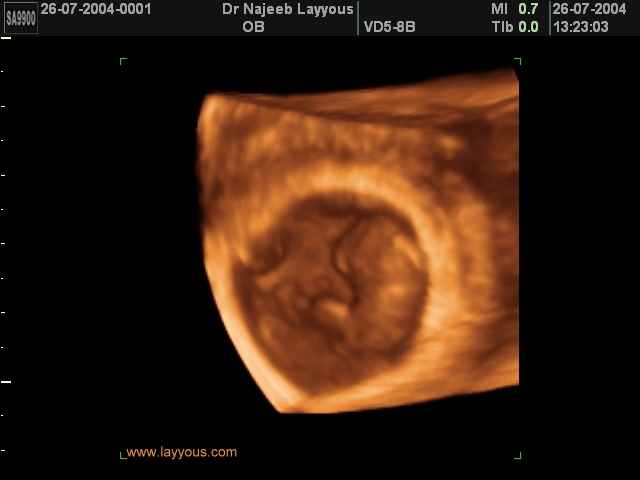

3D First Trimester Ultrasound Scan Photos